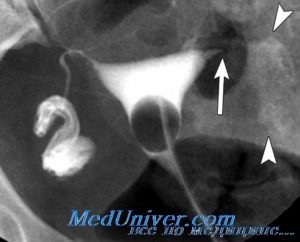

Непроходимостью фаллопиевых труб нарушает продвижения сперматозоидов к яйцеклетке. Она может быть функциональной, в данном случае никаких анатомических изменений не выявляется, но по определенным причинам нарушается функционирование маточных труб, и органической – когда в трубах происходит ряд различного рода изменений, мешающих их проходимости.

Различают частичную и полную непроходимость — гидросальпинкс. В случае частичной — непроходим лишь определенный участок трубы. В случае полной — труба непроходима полностью.

Операция считается самым эффективным способом устранения непроходимости фаллопиевых труб. Результат будет зависеть от степени недуга. В том случае, если спайки распространились по всей трубе, то даже их удаление не поможет возобновить работу органа. Если трубы сильно изменились из-за воспаления, они растянулись, или наполнены большим количеством жидкости, то их удаляют.